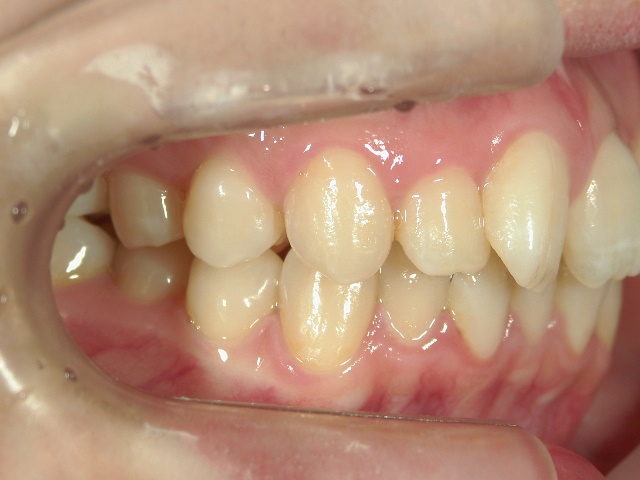

矯正歯科 治療前

no.8_8495_治療前_左.jpgno.8_8495_治療前_正面.jpgno.8_8495_治療前_右.jpg